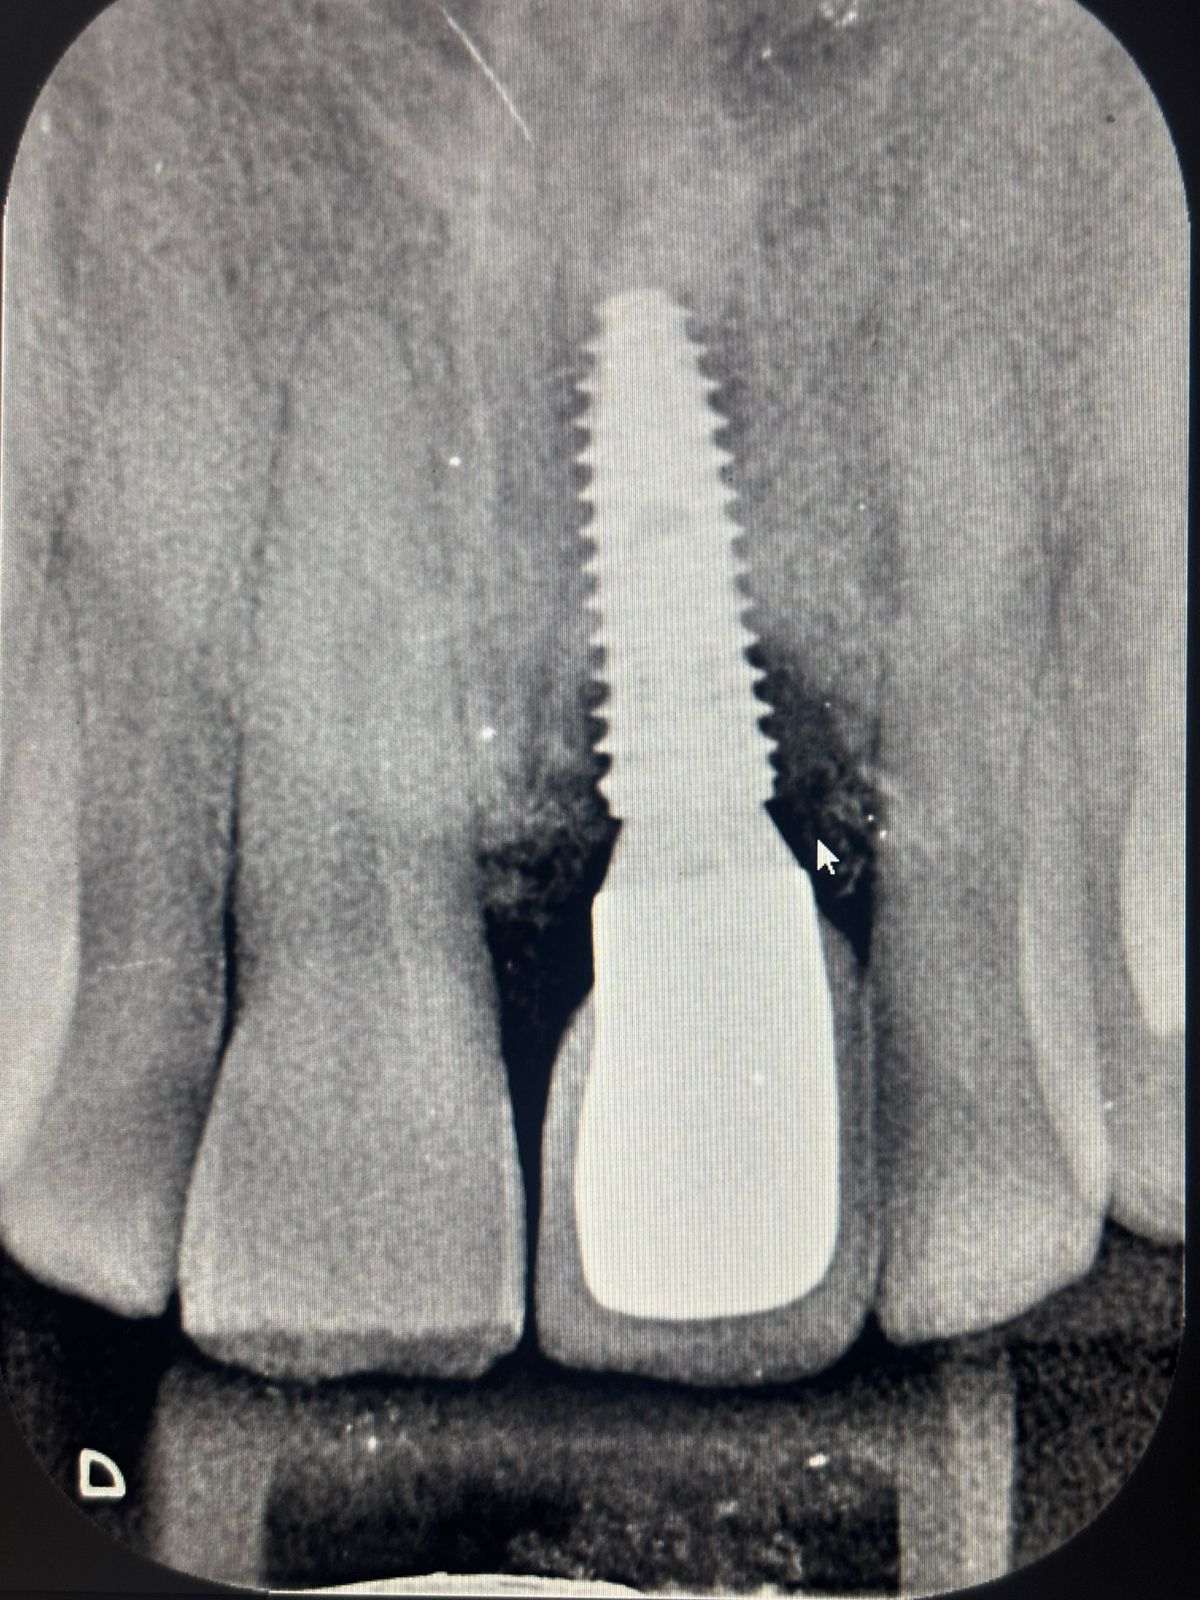

X-ray of patient with implant

Our first step was to take an intraoral periapical (IOPA) X-ray of the implant site. This is standard protocol: before touching anything, we need to understand what we are working with beneath the gumline.

The good news — the implant body appeared stable within the bone. There were no signs of infection around the implant tip, and the abutment was intact. This was not an implant in distress. The crown had simply lost its mechanical retention over time, which is a well-documented occurrence and entirely correctable.

Important Finding — Crestal Bone

However, the X-ray also revealed early crestal bone changes around the implant neck — a finding we do not overlook or minimise. Crestal bone is the portion of the jawbone that sits at the level of the implant shoulder, and minor changes here can be an early indicator of bone remodelling or the beginning of peri-implant stress. Rajesh was informed of this finding clearly and calmly. We explained what it means, what it does not necessarily mean, and why it is important to monitor this going forward. A follow-up review was scheduled, and personalised oral hygiene guidance was provided for maintaining implant health at home. Early awareness is always in the patient's best interest.

This is a reminder that an X-ray taken for one purpose — identifying a loose crown — can simultaneously provide broader clinical intelligence. Every image is an opportunity to see the full picture, and our team is trained to read it that way.